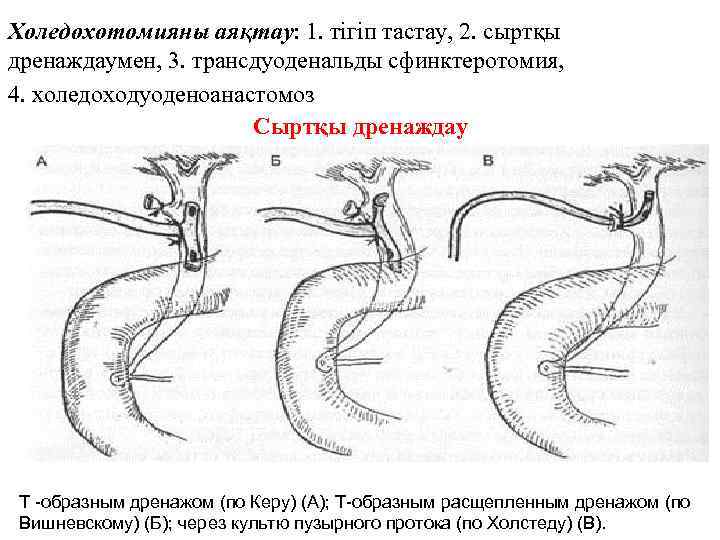

Холедохотомияны аяқтау: 1. тігіп тастау, 2. сыртқы дренаждаумен, 3. трансдуоденальды сфинктеротомия, 4. холедоходуоденоанастомоз Сыртқы дренаждау Т -образным дренажом (по Керу) (А); Т-образным расщепленным дренажом (по Вишневскому) (Б); через культю пузырного протока (по Холстеду) (В).